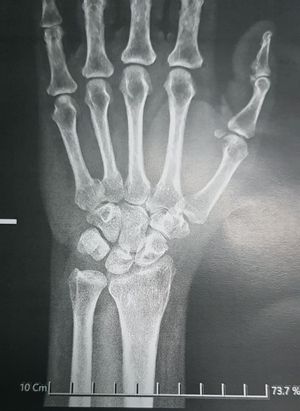

63 ys female that dropped on her left hand and complaine of painful and swelling

Is it scaphoid fracture

The patient have rhumatoid arthritis ๐Ÿ˜ฎ?

Osteoporosis?

Age related

I told that osteoporosis is age related